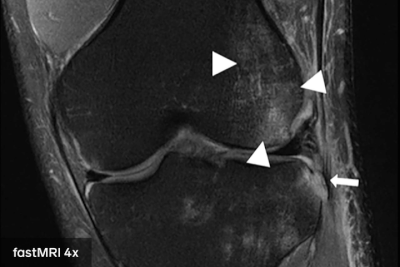

fastMRI团队多年来一直在研究这个问题,但周二他们在《 American Journal of Roentgenology》杂志上发表了一项临床研究,他们说这证明了他们的方法的可信度。该研究要求放射科医生根据传统的核磁共振扫描和人工智能增强的患者膝盖扫描进行诊断。研究报告称,当面对传统扫描和AI扫描时,医生做出的评估完全相同。

“这里可以基于信任的关键词是互换性,”Sodickson说。“我们不是在看一些基于图像质量的量化指标。我们是说,放射科医生做出同样的诊断。他们发现同样的问题。他们不会错过任何东西。”